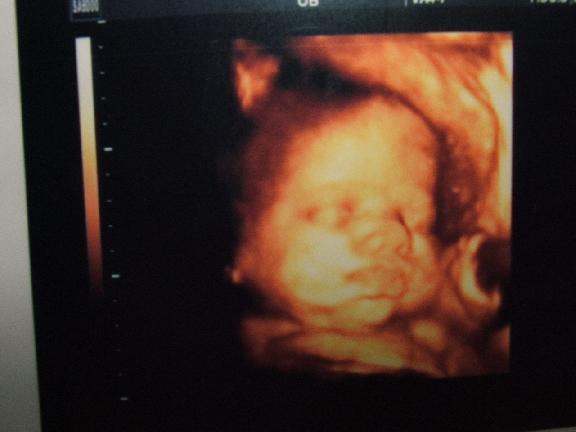

Ma voltunk Uh-n, megpróbálom feltenni nektek a képet, amit kaptunk. Olyan szép lett, teljesen látszik az arca. :) Már nagyon kíváncsi vagyok.

Bpd-je 92-es. :shock: Kis kerek buksis baba lesz. Súlya: 2300gramm.

Az első a két testvér. Zsófi a pocakban, és BOri. Sztem nagyon hasonlítanak.

Ez pedig a tegnapi uh kép:

Lili, milyen jok ezek az uh kepek! Nagyon jol latszik Boti arca! :D Tenyleg nagyon hasonlit Zsofira! :D

Lili: aztaa , hogy te milyen csuda szuper képet kaptál Botikáról! Mintha nem is a pocakban lenne. Szerintem is nagyon hasonlítanak egymásra Zsófikával. Az első 2 kép olyan mintha egy babáról készült volna... :shock: :wink: :lol: :lol: :lol:

Egyébként Erszényke, olyan érdekes, mert Boti szinte mindig mutatja az arcát uh-n. A nőgyógyász is ugye megnéz uh-val a havi kontrollokon, és ott is mindig mutatja a doki, h. nézze, ott van az arca. Telibe mindig. ÉS nem gondoltam volna, h. most itt is sikerül elkapni. Még csücsörített is. :)